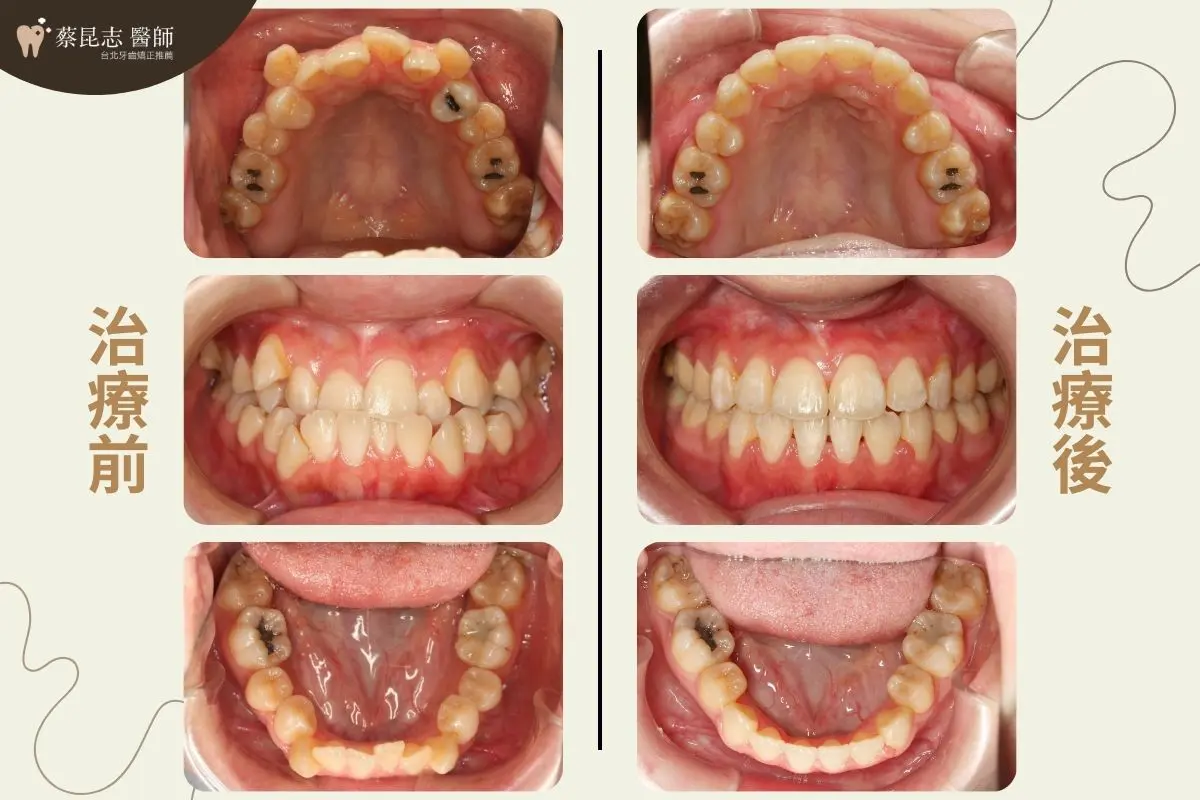

治療前可以見到因為上下顎前牙嚴重擁擠、上顎高位犬齒,所造成的不美觀笑容。

又因為下顎前牙過於外暴、上下顎前牙咬合與正常咬合相反的錯咬,所造成的側面輪廓下唇的部分過於外凸。

治療計畫是拔除上、下顎左右兩側各一顆第一小臼齒,讓嚴重擁擠上下顎前牙,有空間可以排整齊

將上、下顎前牙後縮,恢復上下顎前牙正常咬合,並改善側臉輪廓下唇過於外凸之外觀,讓側臉下巴輪廓線條更加協調。

前牙錯咬戽斗案例-結果分享

前牙錯咬戽斗矯正前後臉型變化 前牙錯咬戽斗矯正前後口腔變化 前牙錯咬戽斗矯正前後口腔側面變化 前牙錯咬戽斗矯正前後門牙變化 前牙錯咬戽斗矯正前後嘴型變化 前牙錯咬戽斗矯正前後正面x光變化 前牙錯咬戽斗矯正前後側面x光變化